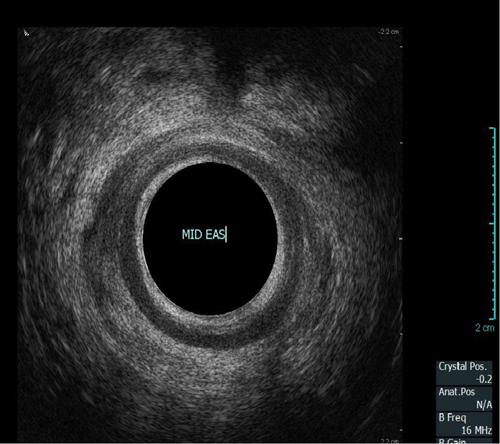

Endoanal ultrasound

This procedure is indicated for assessment of the anal sphincter in patients with incontinence. This allows evaluation of the internal and external anal sphincters (sphincter thickness, length and scarring). It is pertinent to obtain history of obstetric trauma as well as any surgeries / intervention to aid assessment.

As with the proctogram technique, the procedure is explained in detail and consent obtained prior, and the presence of a chaperone makes the patient more comfortable. Digital rectal examination is performed as a reference to assess anal tone. Still images as well as cine of the ultrasound are taken to assess the sphincter complex (Figure 3).

Figure 3a: (Top, middle and bottom) Normal endoanal ultrasound.

Figure 3b: Abnormal / deficient low internal anal sphincter.

Figure 3c: High External anal sphincter scars due to obstetric trauma.